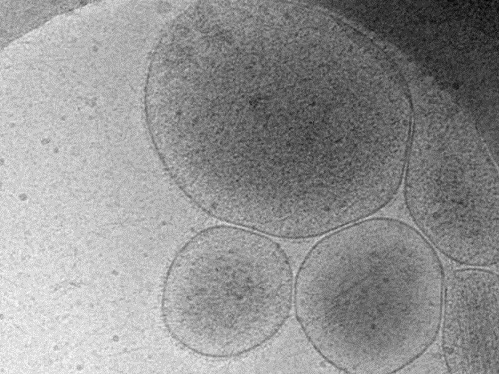

Aim of the project is to set up standardized protocols for the isolation of highly pure extracellular vesicle (EV) fractions from complex biological matrices, such as human blood or plasma, and to investigate the application of Nano Electrospray Gas-phase Electrophoretic Mobility Molecular Analysis (nES-GEMMA) for the characterization of EVs, in particular exosomes, with respect to quantification, which is potentially superior to indirect quantification based on protein concentration as used to date. We will assess for the first time whether protein and lipid content are qualitatively influenced by the size of extracellular vesicles by collecting size separated vesicles via an electrostatic nanometer aerosol sampler. Furthermore, eventual modifications in the composition of vesicles obtained from physiological and different pathological settings will be monitored.